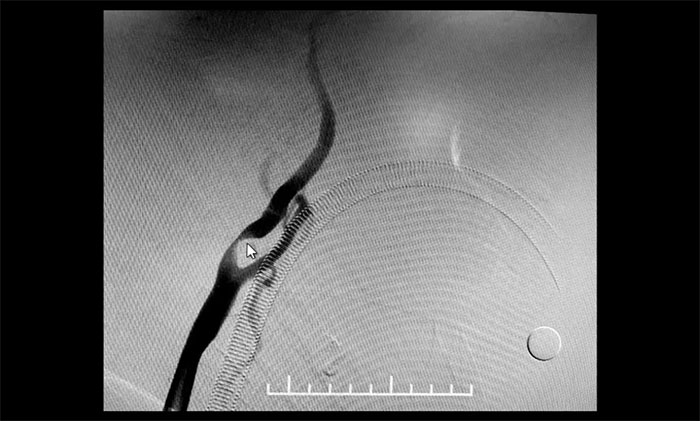

颈内动脉狭窄可分为轻度(<50%),中度(50%~69%)和重度(70%~99%),椎动脉狭窄的判别标准与之相仿。DSA检查示:患者双侧颈内动脉及左侧椎动脉存在重度狭窄,狭窄程度达到甚至超过90%,病情十分严重,遂立即收治入院。

▲ 双侧颈内动脉及左侧椎动脉重度狭窄